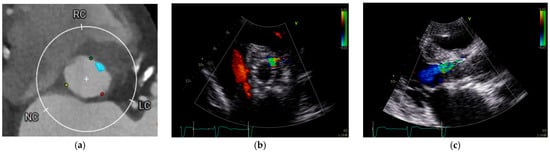

However, not only the quantity but also the distribution of calcification plays a key role. The presence of calcifications in the leaflets, annulus, and left ventricular outflow tract (LVOT), as well as asymmetric patterns of deposition, have all been independently associated with increased PVL risk [9,10,11]. The eccentricity index, calculated as [1 − (Dmin/Dmax)], where Dmin and Dmax represent the smallest and largest orthogonal diameters of the aortic annulus as measured by multislice computed tomography (MSCT), is another important predictor when >0.25 [12]. Moreover, bicuspid aortic valve morphology and extreme annular dimensions (either small or large) further contribute to higher PVL incidence. Other anatomical risk factors include discrepancy between LVOT and annulus diameter (leading to poor prosthesis apposition) and a steep aorto-LVOT angulation, which may alter radial deployment forces and stent geometry [13,14,15]. Table 1 presents the principal risk factors for PVLs. Figure 1 shows an example of correlation between pre-implantation annular calcification and residual PVL after TAVR.

Figure 1. Annular calcification and residual PVL after TAVR. (a) Cardiac computed tomography performed for pre-TAVR planning revealed an annular calcification located at the level of virtual basal ring between the left and right coronary cusps. (b,c) Following TAVR, an anterior paravalvular leak persisted at the site of the previously documented calcification, approximately at the 1 o’clock position.